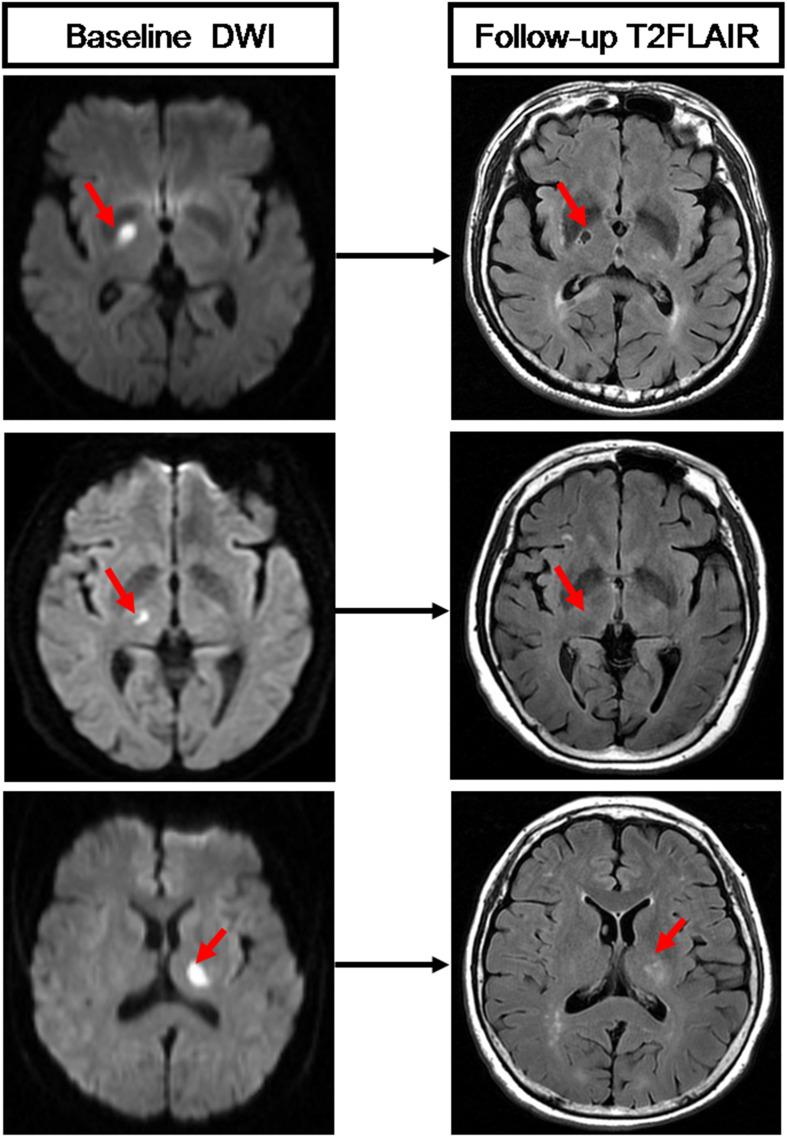

Recent small subcortical infarcts (RSSIs) can occur in different brain regions. Distinct etiologies might be involved for RSSIs in different locations and could further affect RSSI cavitation and functional outcomes. In this study, we aim to analyze the baseline clinical and imaging characteristics associated with the occurrence and cavitation of RSSIs in different locations. We retrospectively include patients who presented with RSSIs from a database for cerebral small vessel disease. Detailed information, including demographic, clinical, laboratory, and radiological data, were collected. We identify baseline RSSIs on diffusion-weighted images and divide them into brainstem, subcortical white matter, and basal ganglia region groups. Cavitation is evaluated on follow-up T2 fluid-attenuated inversion recovery (FLAIR) images. Statistical analysis is performed to determine factors associated with the occurrence and cavitation of RSSIs in different locations. We find that patients with brainstem RSSIs have a higher proportion of diabetes (64.1%) compared to patients with subcortical white matter (27.3%, < 0.001) and basal ganglia region RSSIs (35.2%, = 0.006) and have higher levels of HbA1c (7.20%) compared to patients with subcortical white matter (6.10%, = 0.001) and basal ganglia region RSSIs (6.20%, = 0.003). In addition, patients with brainstem RSSIs have higher NIHSS scores than patients with subcortical white matter RSSIs (2 vs 0, = 0.001). Patients with subcortical white matter RSSIs have higher a white matter hyperintensity (WMH) burden compared to patients with basal ganglia region RSSIs (21.64 cm vs 11.10 cm, = 0.004). Follow-up analysis demonstrates that basal ganglia region RSSIs are less likely to cavitate than subcortical white matter RSSIs (61.4% vs 83.6%, = 0.010), and contacting with WMH is associated with the cavitation of subcortical white matter RSSIs (OR: 101.760, = 0.003). Our study demonstrates that RSSIs in different locations are associated with different clinical and imaging characteristics. Furthermore, cavitation of RSSIs might be affected by local lesion features and the surrounding environment rather than general demographic and clinical factors.

近期皮质下小梗死灶(RSSIs)可发生于不同脑区。不同部位的RSSIs可能涉及不同病因,且可能进一步影响RSSIs的空洞形成及功能转归。在本研究中,我们旨在分析与不同部位RSSIs的发生及空洞形成相关的基线临床和影像学特征。我们回顾性纳入了来自脑小血管病数据库中出现RSSIs的患者。收集了详细信息,包括人口统计学、临床、实验室及放射学数据。我们在扩散加权图像上识别基线RSSIs,并将其分为脑干、皮质下白质和基底节区组。在随访的T2液体衰减反转恢复(FLAIR)图像上评估空洞形成情况。进行统计分析以确定与不同部位RSSIs的发生及空洞形成相关的因素。我们发现,与皮质下白质RSSIs患者(27.3%,P<0.001)及基底节区RSSIs患者(35.2%,P = 0.006)相比,脑干RSSIs患者糖尿病比例更高(64.1%);与皮质下白质RSSIs患者(6.10%,P = 0.001)及基底节区RSSIs患者(6.20%,P = 0.003)相比,脑干RSSIs患者糖化血红蛋白(HbA1c)水平更高(7.20%)。此外,脑干RSSIs患者的美国国立卫生研究院卒中量表(NIHSS)评分高于皮质下白质RSSIs患者(2分对0分,P = 0.001)。与基底节区RSSIs患者相比,皮质下白质RSSIs患者的白质高信号(WMH)负荷更高(21.64 cm对11.10 cm,P = 0.004)。随访分析表明,基底节区RSSIs比皮质下白质RSSIs空洞形成的可能性更小(61.4%对83.6%,P = 0.010),且与WMH接触与皮质下白质RSSIs的空洞形成相关(比值比:101.760,P = 0.003)。我们的研究表明,不同部位的RSSIs与不同的临床和影像学特征相关。此外,RSSIs的空洞形成可能受局部病变特征及周围环境影响,而非一般人口统计学和临床因素。